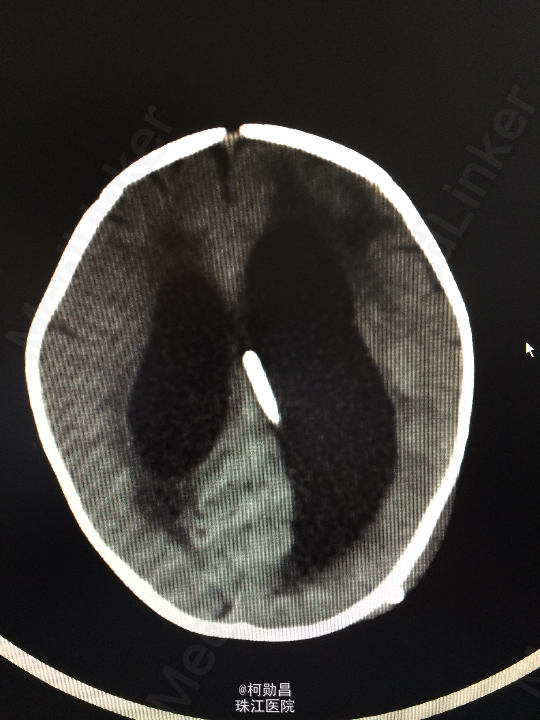

查体:神志不清,四肢肌力增高 辅助检查:头颅CT提示脑积水并脑脊液外渗,幕上脑室扩张,右侧额颞叶硬膜下脑脊

诊断:化脓性脑膜炎伴脑积水 处理:予内科抗感染治疗,后行脑室腹腔引流术。